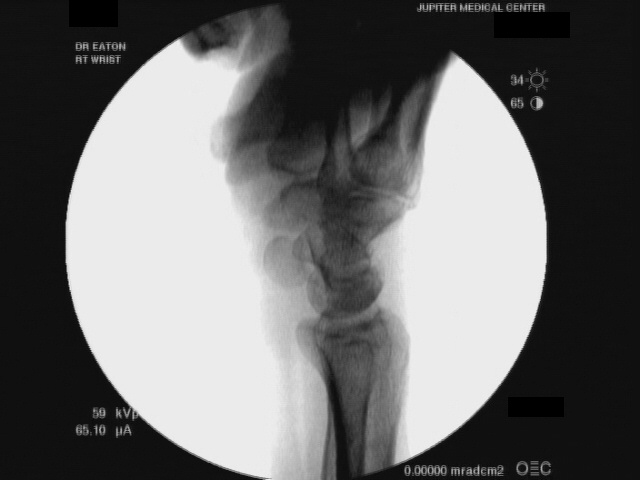

ataxia. Xrays show scapholunate dissociation with dorsal scaphoid

rotation: |

| Minimal passive

manipulation results in dorsal lunate dislocation which can be reduced

easily, all without pain: |